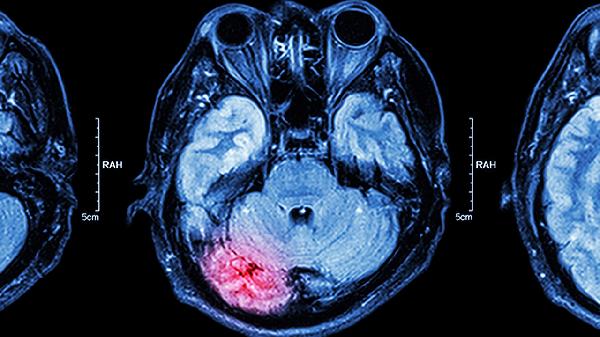

脑力下降可能由多个原因引起,常见的包括:遗传因素(如家族中有智力障碍或神经退行性疾病的病例)、环境因素(如过度压力、睡眠不足或长期缺乏刺激性活动)、生理因素(如甲状腺功能低下、慢性疲劳或血糖偏低)、外伤(如脑部损伤导致的功能性障碍)、以及病理问题(如阿尔茨海默病、帕金森病等神经系统退行性疾病)。这些原因可能以不同程度影响注意力、学习能力及问题解决能力。

要改善这些问题,可以从生活习惯、饮食调节及专业治疗等多个方面入手。充足的睡眠(7-9小时)是大脑高效运作的基础,尤其在巩固记忆和修复神经时尤为重要。均衡营养摄入,如深海鱼、坚果、全谷物和富含抗氧化物质的蔬菜水果,有助于维持脑组织的健康。同时,通过规律的有氧运动(如快走、游泳)和脑力训练(如记忆技巧、自我学习新技能)可以提高脑细胞的活跃性。对于因明确病理问题引起的脑力减退,药物治疗是必要的选择,例如胆碱酯酶抑制剂适用于阿尔茨海默病,左旋多巴可以缓解帕金森症状,而针对甲状腺疾病的激素治疗可恢复正常脑功能。